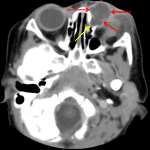

- Peripherally enhancing fluid collection along the left medial canthus with overlying periorbital skin thickening and an ill-defined collection extending inferiorly from the anterior surface of the left globe

- Dilated proximal left nasolacrimal duct which tapers to normal caliber at the distal third

- No retrobulbar collection or stranding. No proptosis

- Dacryocystitis

Peripherally enhancing fluid collection along the left medial canthus measuring 2 x 1.5 x 1.8 cm with surrounding inflammatory changes, consistent with dacryocystitis. Ophthalmology consultation is recommended.

Ill-defined collection extending inferiorly from the anterior surface of the left globe could be reactive, although this could represent an additional site of infection/developing abscess. Recommend correlation with exam.

Left preseptal cellulitis without retrobulbar stranding or proptosis to suggest postseptal orbital cellulitis.